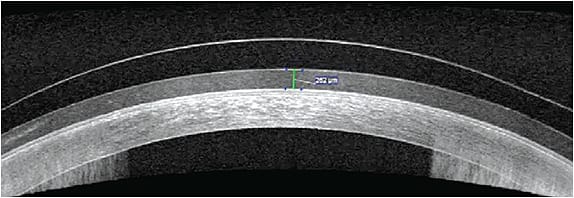

When fitting SLs, the diameter of the SL for patients who have dry eye disease is often dependent on the surface area that needs rehabilitation. The larger the diameter of the lens, the more advanced haptics may be required due to the asymmetry of the sclera. Corneoscleral mapping may be beneficial in these cases to provide further understanding of the ocular surface shape, particularly for those patients who have significant cornea and conjunctival irregularities (Figures 2 and 3). Other patients may benefit from impression-based SL technology, especially as much of our mapping software relies on a decent quality tear film to get a reliable image.